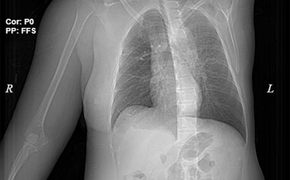

Tuy nhiên hiện nay việc sàng lọc ung thư chưa được bảo hiểm y tế chi trả. Do đó Bộ Y tế đang xây dựng luật Khám chữa bệnh sửa đổi, dự kiến bổ sung BHYT chi trả sàng lọc cho một số loại ung thư nhiều người mắc như phổi, gan, vú, dạ dày…